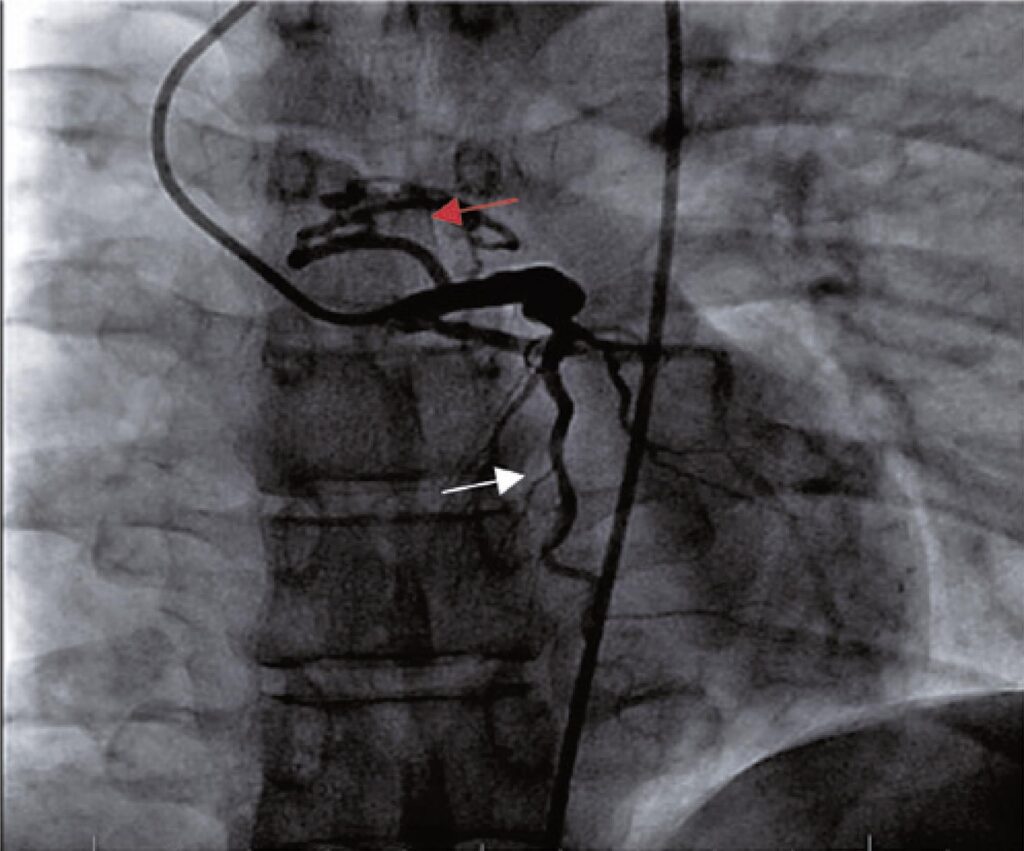

Fístula da artéria descendente anterior para artéria pulmonar

As anomalias congênitas e, dentre elas, as variações anatômicas das artérias coronarianas, embora pouco frequentes, são cada vez mais estudadas e diagnosticadas devido à estreita relação de sintomas, tais quais angina, dispneia, síncope ou arritmias em pessoas jovens sem comorbidades. Este trabalho teve como objetivo principal apresentar o estudo de caso de um paciente com sintomas isquêmicos secundários à malformação de uma artéria coronariana. Descrevem-se o momento da admissão do paciente, o diagnóstico mediante exames complementares e a resolução terapêutica do caso. As fístulas coronarianas, apesar de terem uma baixa incidência entre as cardiopatias congênitas, tornaram-se cada vez mais frequentes, sendo melhor caraterizadas devido aos novos métodos diagnósticos.